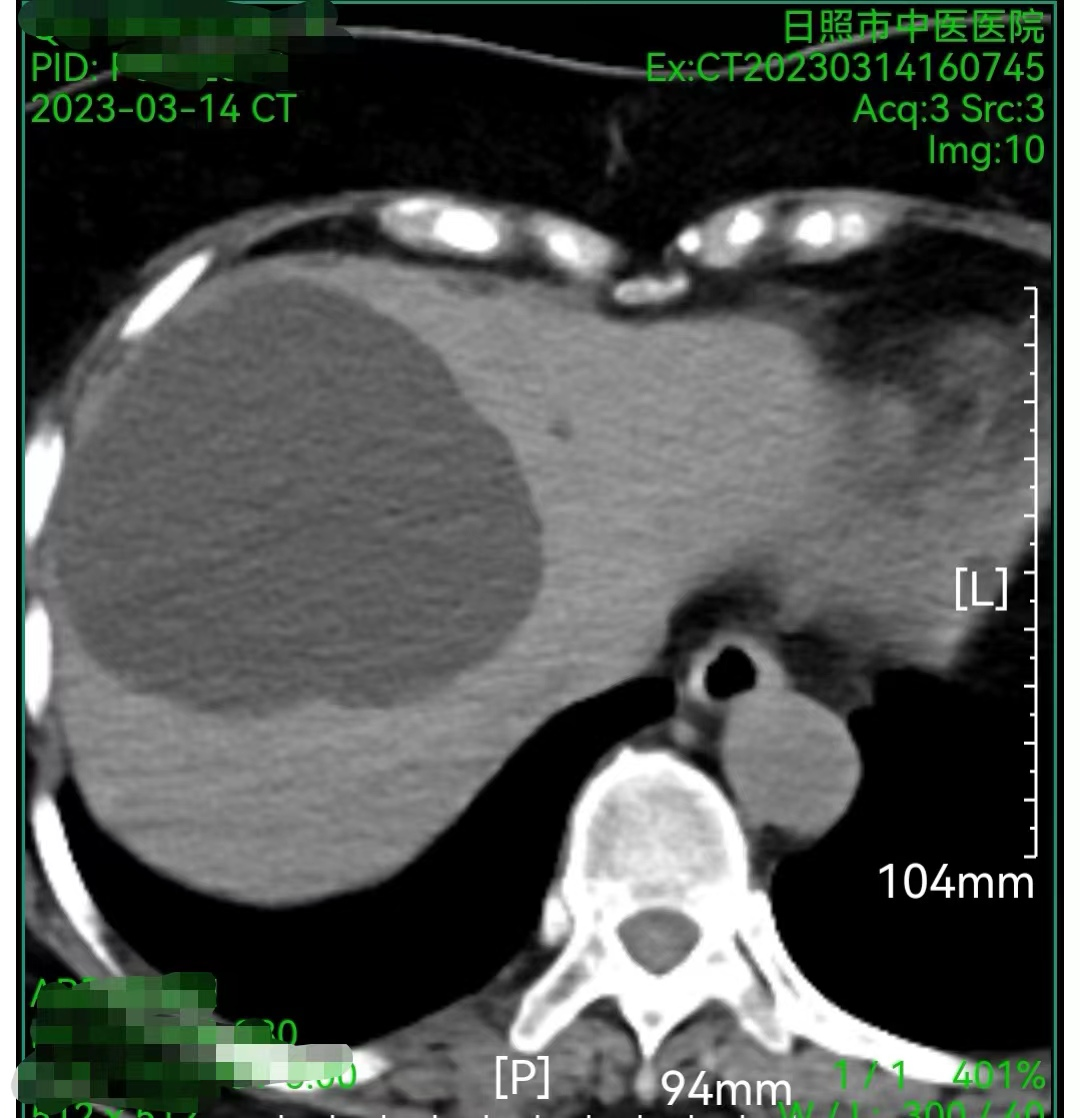

图3.出院前两天复查。

在医护人员的精心治疗及照护下,患者症状完全缓解,复查囊肿囊壁已完全塌陷,饮食情况恢复正常,达到出院指征后带管出院,拟2周后复查无特殊予拔出穿刺引流管。